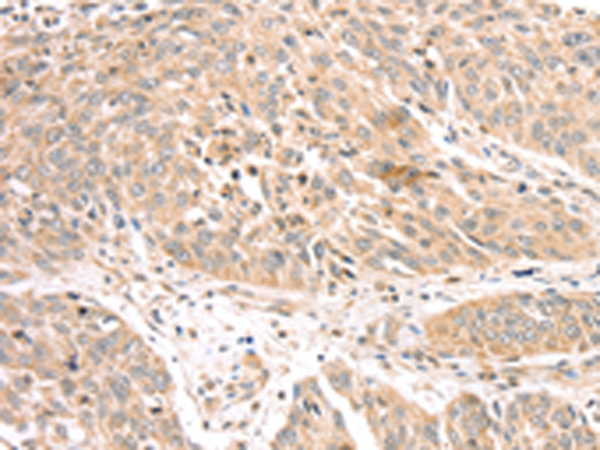

分类: 科研抗体货号: P01696别名:应用: WB,IHC反应种属: Human, Mouse

分类: 科研抗体货号: P01727别名: CT145; PRTD-NY2应用: WB,IHC反应种属: Human

分类: 科研抗体货号: P01726别名:应用: WB,IHC反应种属: Human